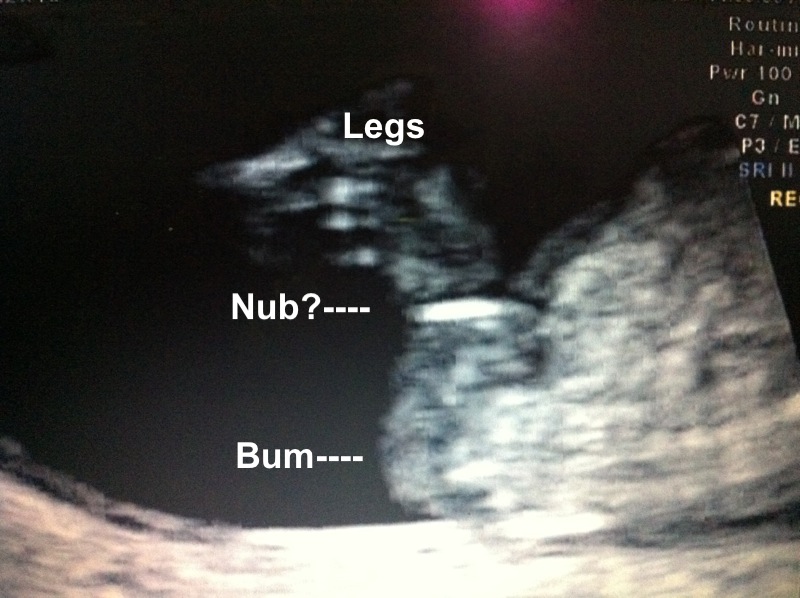

UPDATE 20 weeks photo added

Here is my scan at 12w 4d but baby measured at 13w 1d baby would not sit still so couldnt get a clear shot i went through ultrasound and this is what i found would love to hear what you think thanks guys